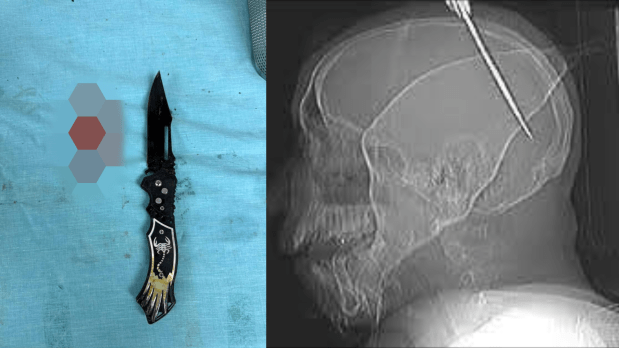

Man stabbed in the brain with a knife and live

๐‹๐ข๐Ÿ๐ž ๐’๐š๐ฏ๐ž๐ ๐›๐ฒ ๐„๐ฆ๐ž๐ซ๐ ๐ž๐ง๐œ๐ฒ ๐๐ž๐ฎ๐ซ๐จ๐ฌ๐ฎ๐ซ๐ ๐ข๐œ๐š๐ฅ ๐ˆ๐ง๐ญ๐ž๐ซ๐ฏ๐ž๐ง๐ญ๐ข๐จ๐ง ๐€๐Ÿ๐ญ๐ž๐ซ man was stabbed in the head with a knife,

A Cuban national, 19 years old male, was rushed to the hospitalโ€™s emergency room after sustaining a violent stab wound to the head during an altercation at a social gathering. Upon arrival, he was seen with a knife deeply embedded in his skull, a rare and highly dangerous form of penetrating brain injury. Such cases are exceptionally critical, as any movement of the object can result in catastrophic bleeding, irreversible brain damage, and death. Within minutes, the patient was stabilized,

The scans revealed that the knife had penetrated the cranial vault and entered the brain, lacerating tissues in the speech center of the brain with active intracranial bleeding.